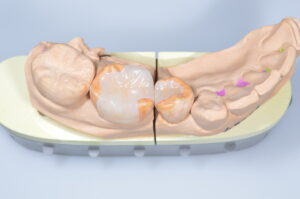

治療途中

| 治療内容 | 銀歯を白くしたいという希望に対して、e.maxによるセラミック治療と、CR充填を行なった。 1回目に左下の小さな銀歯を除去してCR充填、2回目に右下の大きめの銀歯を除去して仮詰めを実施。3回目に型取りを行い、4回目にセラミックインレー(e.max)を装着した。 |